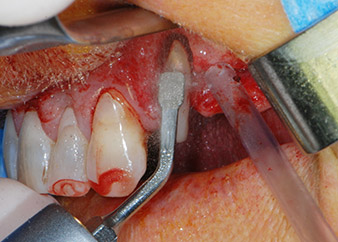

One month later, on the day of surgery, pain and inflammation at tooth 24 were minimal, but mobility of Miller class 2 was still present. After opening the flaps and cleaning the periapical and peri radicular infected tissue, the extent of the bone defect became obvious (Figs. 2 and 3).

At the buccal root, all vestibular and distal bone was missing. Attachment was essentially restricted to the palatal root, underlining the preliminary poor prognosis. Tooth 27 also showed a reduced horizontal attachment and a minimal apical rarefaction (cf. Fig. 1) without clinical symptoms.

total loss of bone and attachment

Fig. 2 and 3: After raising flaps, one month after endodontic revision and initiation of full-mouth periodontal therapy, the buccal root of tooth 24 showed a total loss of bone and attachment.

Prior to implant placement, infected tissue was removed from the alveolar bone in the implant site and around the abutment teeth with an insert originally designed for bone shaping and collecting bone chips (Piezomed, insert B5) (Figs. 6 and 7).

piezo-electric scraping instrument

Fig. 6: The surgical site was debrided with a piezo-electric scraping instrument designed for collecting bone particles and modeling bone.

osseous defects

Fig. 7: After cleaning the osseous defects mesial to tooth 27 and around the root of tooth 24 were clearly visible.